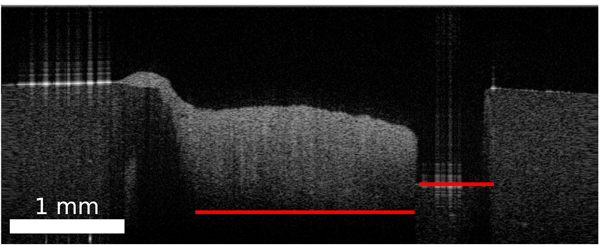

Standard image High-resolution imageFigure 7. Depth of the agarose shape in the OCT B-scan varies with the axial position and thickness of the tissue due to differences in the refractive index along the depth axis.

Download figure:

Standard image High-resolution imageA transformation had to be determined for the transfer of the labels from the histology image onto the corresponding OCT image. The transformation is based on the outer shape of the sample. Due to the different image modalities and varying grade of details shown in the images, the use of intensity based features was not feasible. The outer shape of the tissue imprinted by the agarose hole is assumed to be similar in the OCT image and in the histological cut. The first part of the processing is the extraction of the tissue part from the histological image and the corresponding OCT image as binary mask which contain the information of the outer tissue shape. For the histological image the tissue was extracted based on the colour difference between the stained tissue and the white background. Locating and extracting the brain tissue in the OCT images took a few more steps: Each OCT image was processed through the already mentioned U-Net, which results in a binary mask. The columns of the mask were set to 0, if a column showed agarose in the original OCT image. The vertical margins were set manually by marking the left and right edge of the tissue in the OCT image, which was clearly distinguishable from the agarose. The pixel location of the bottom of the agarose imprint needed to be estimated, because the border between agarose and tissue was not visible due to the depth signal decay of the OCT image. This pixel location depends on the ratio of air and tissue. Since this ration changes over the OCT image, the location had to be determined for each image column. The axial pixel size Δs is scaled with the inverse refractive index of the medium n ( ). Figure 7 shows this effect unambiguously. If the agarose imprint is only filled with air (nair

= 1), the bottom of the agarose imprint appears higher in the OCT image whereas a composition of tissue (ntissue

> 1) appears lower.

). Figure 7 shows this effect unambiguously. If the agarose imprint is only filled with air (nair

= 1), the bottom of the agarose imprint appears higher in the OCT image whereas a composition of tissue (ntissue

> 1) appears lower.

The composition of air and tissue was determined from the binary mask. Since the composition of the brain tissue is unknown, it was assumed to have a constant refractive index of nt = 1.36 (Gottschalk 1992, Müller and Roggan 1995, Honda et al 2018). The actual depth d can be determined by the sum of all scaled pixel sizes:

Here z was defined as the axial pixel position within the image column. For each column of the binary mask pixels were set to 0 after the depth of the agarose imprint was reached. This results in a mask which marks the tissue content of the OCT image (figure 6).